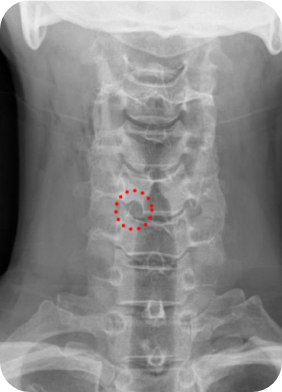

경추 전방,후방 추간공확장술은 해당 병변을 제거하고 나머지 디스크는 제거하지 않고 되도록 유지한 후 신경공만 넓혀주는 수술법입니다.

대개 목디스크 수술이라고 하면 경추 사이에 있는 디스크를 모두 제거하고 그 안에 인공뼈나 인공디스크를 삽입하여 인접부위에 문제를 야기시키기도 하는데, 이를 보완하여 그 마디를 유지하고 신경공만 넓혀주는 수술입니다. 경추와 흉추 사이에 디스크 발생시, 가슴 뼈가 수술부위를 가리는 경우 아주 유용하게 선택할 수 있는 방법입니다.